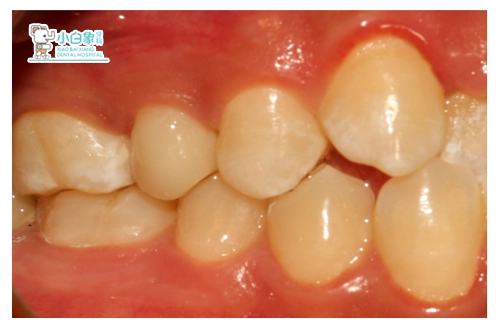

治疗:15去除根管内充填材料及腐质,寻两根管,测根长19mm,M3根备,超声荡洗,隔湿干燥,热牙胶充填根管,在颊侧根管制备桩道,3M纤维桩粘结。

制备牙体,取像,设计,制作高嵌体,试戴,粘结。

戴牙